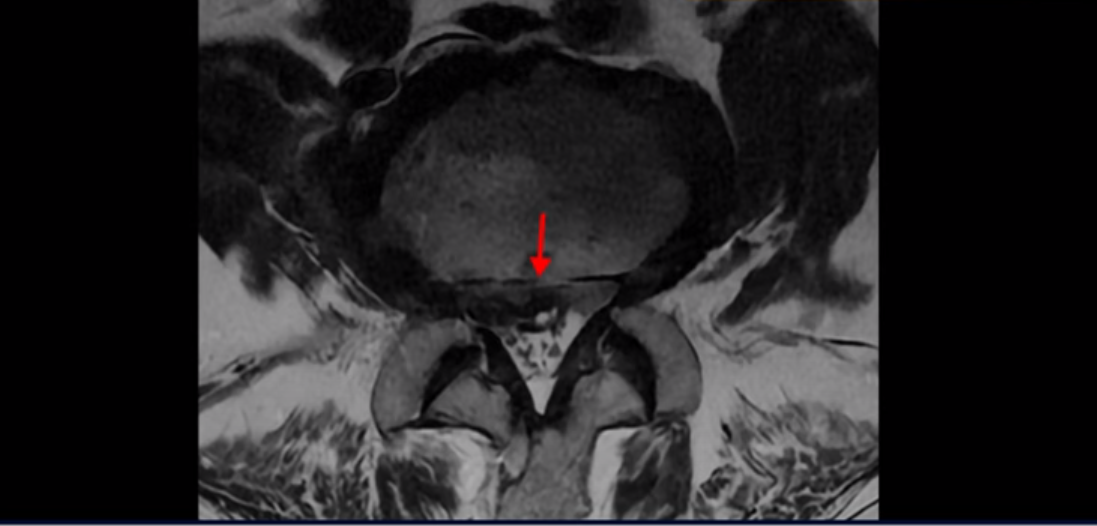

MRI를 보면 허리 4마디가 심하게 퇴행되어 있고

3번 뼈는 넘어질 때 생긴 압박골절이 있습니다.

3번 4번에는 척추관협착과 디스크 탈출이 보이고

4번 5번에는 척추관협착과 심한 디스크 파열이 있습니다.

5번 1번에는 뼈가 자라난 골극이 있고

기립근의 지방화도 심합니다. 또 3번 4번 마디에서는 신경가지가 빠져나가는 추간공이 왼쪽, 오른쪽 모두 많이 좁아져 있습니다.

이런 이유로 이 환자분은 왼쪽 다리는 마비가 생겨 힘이 빠지고 오른쪽 다리에는 심한 방사통이 있어서 휠체어까지 타야 하는 상태가 되었습니다. 이렇게 심하니까 대학병원에서 여러 마디 나사를 박는 유합술을 권유 받으셨는데요.